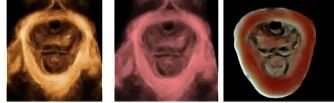

煊影成像技术:使三维图像更加逼真(早、中、晚孕期)

VOlusonE什么彩超机世界顶级四维彩超机美国 GE Voluson E10 BT20金标版落户吉林省吉林中西医结合医院_https://www.jmylbn.com_新闻资讯_第8张

四维超声模式下输出功率指数与二维超声模式下相同,对胎儿无任何伤害